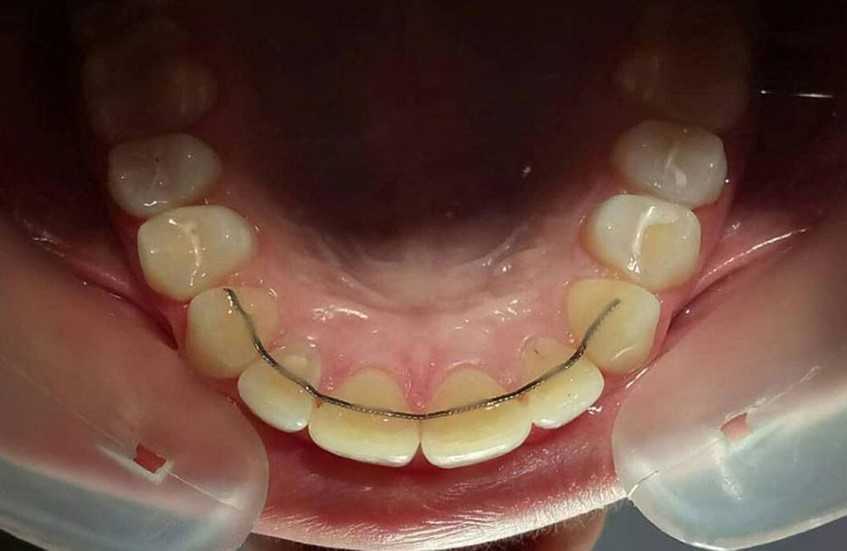

Это самое основное. Устанавливать ли ретейнер – тонкую и малозаметную проволоку, похожую на дугу брекетов, которую крепят с внутренней стороны зубов – решает врач, но чаще всего это делают.

Установленный на зубы ретейнер

Ретейнеры не отменяют также ношения кап. Капы используют те, кто носил брекеты, и продолжают носить те, кто лечился с помощью элайнеров. Обычно капы достаточно надевать на ночь. Их изготавливают по модели зубов в самом конце лечения, когда получен желаемый результат.